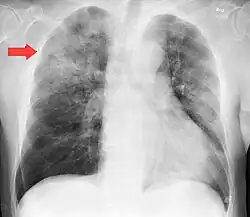

Clinical features of a respiratory tract infection may include initial symptoms of an upper respiratory tract infection mimicking a viral infection, usually associated with low-grade fevers. This may progress to the lower respiratory tract within a few days, with features often resembling those of wheezy bronchitis. Sputum may be difficult to expectorate and is often grey or creamy in color. The cough may persist for weeks without appropriate treatment. Many cases are diagnosed after presenting chest infections that do not respond to penicillins or first-generation cephalosporins. A chest X-ray can identify alveolar consolidation.[36]